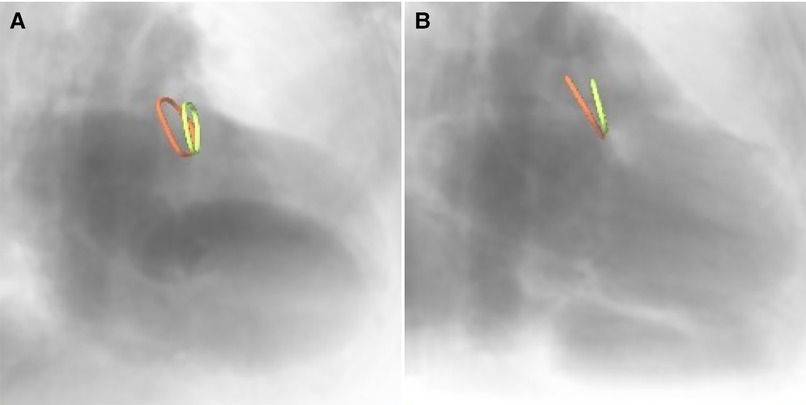

Furthermore, the optimal XR angulations were predicted from the CMR identified landing zones yielding orthogonal projection of the maximal diameter (Figure 3) independently by two readers. Angulations deviating by more than the 95% confidence interval were considered different to identify optimal angulations outside of the recommended angulation range (RAO20-30/CAUD20-30).

Figure 3. CMR-derived ostium (red) and landing zone (green) superimposed onto angiographical simulation in (A) the recommended angulation and (B) patient-specific optimal angulation.